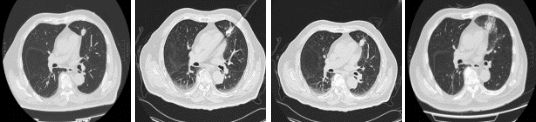

从左至右:消融前、消融中、消融中、消融后一天

从手术开始到结束,仅耗时35分钟。陈老伯安返病房,生命体征平稳。术后陈老伯状态良好,CT显示病灶区域密度增高,消融范围完美覆盖了病灶,而周边的肺组织安然无恙。